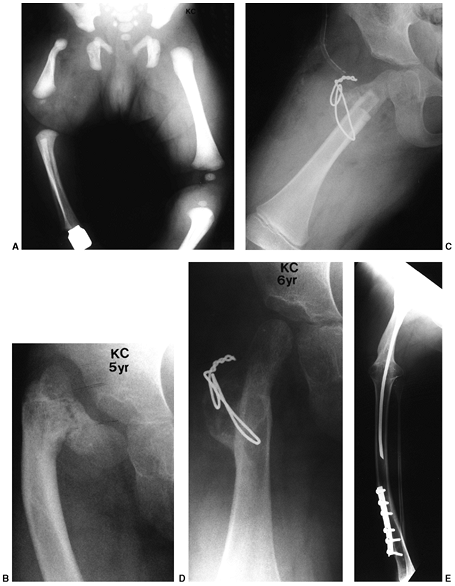

Figure 31.2 A, B:

The end of the tibia with the bony overgrowth removed and the head of the fibula inserted into the medullary canal of the tibia (Marquardt procedure). C: The anteroposterior view of the tibia 6 weeks after the procedure. |